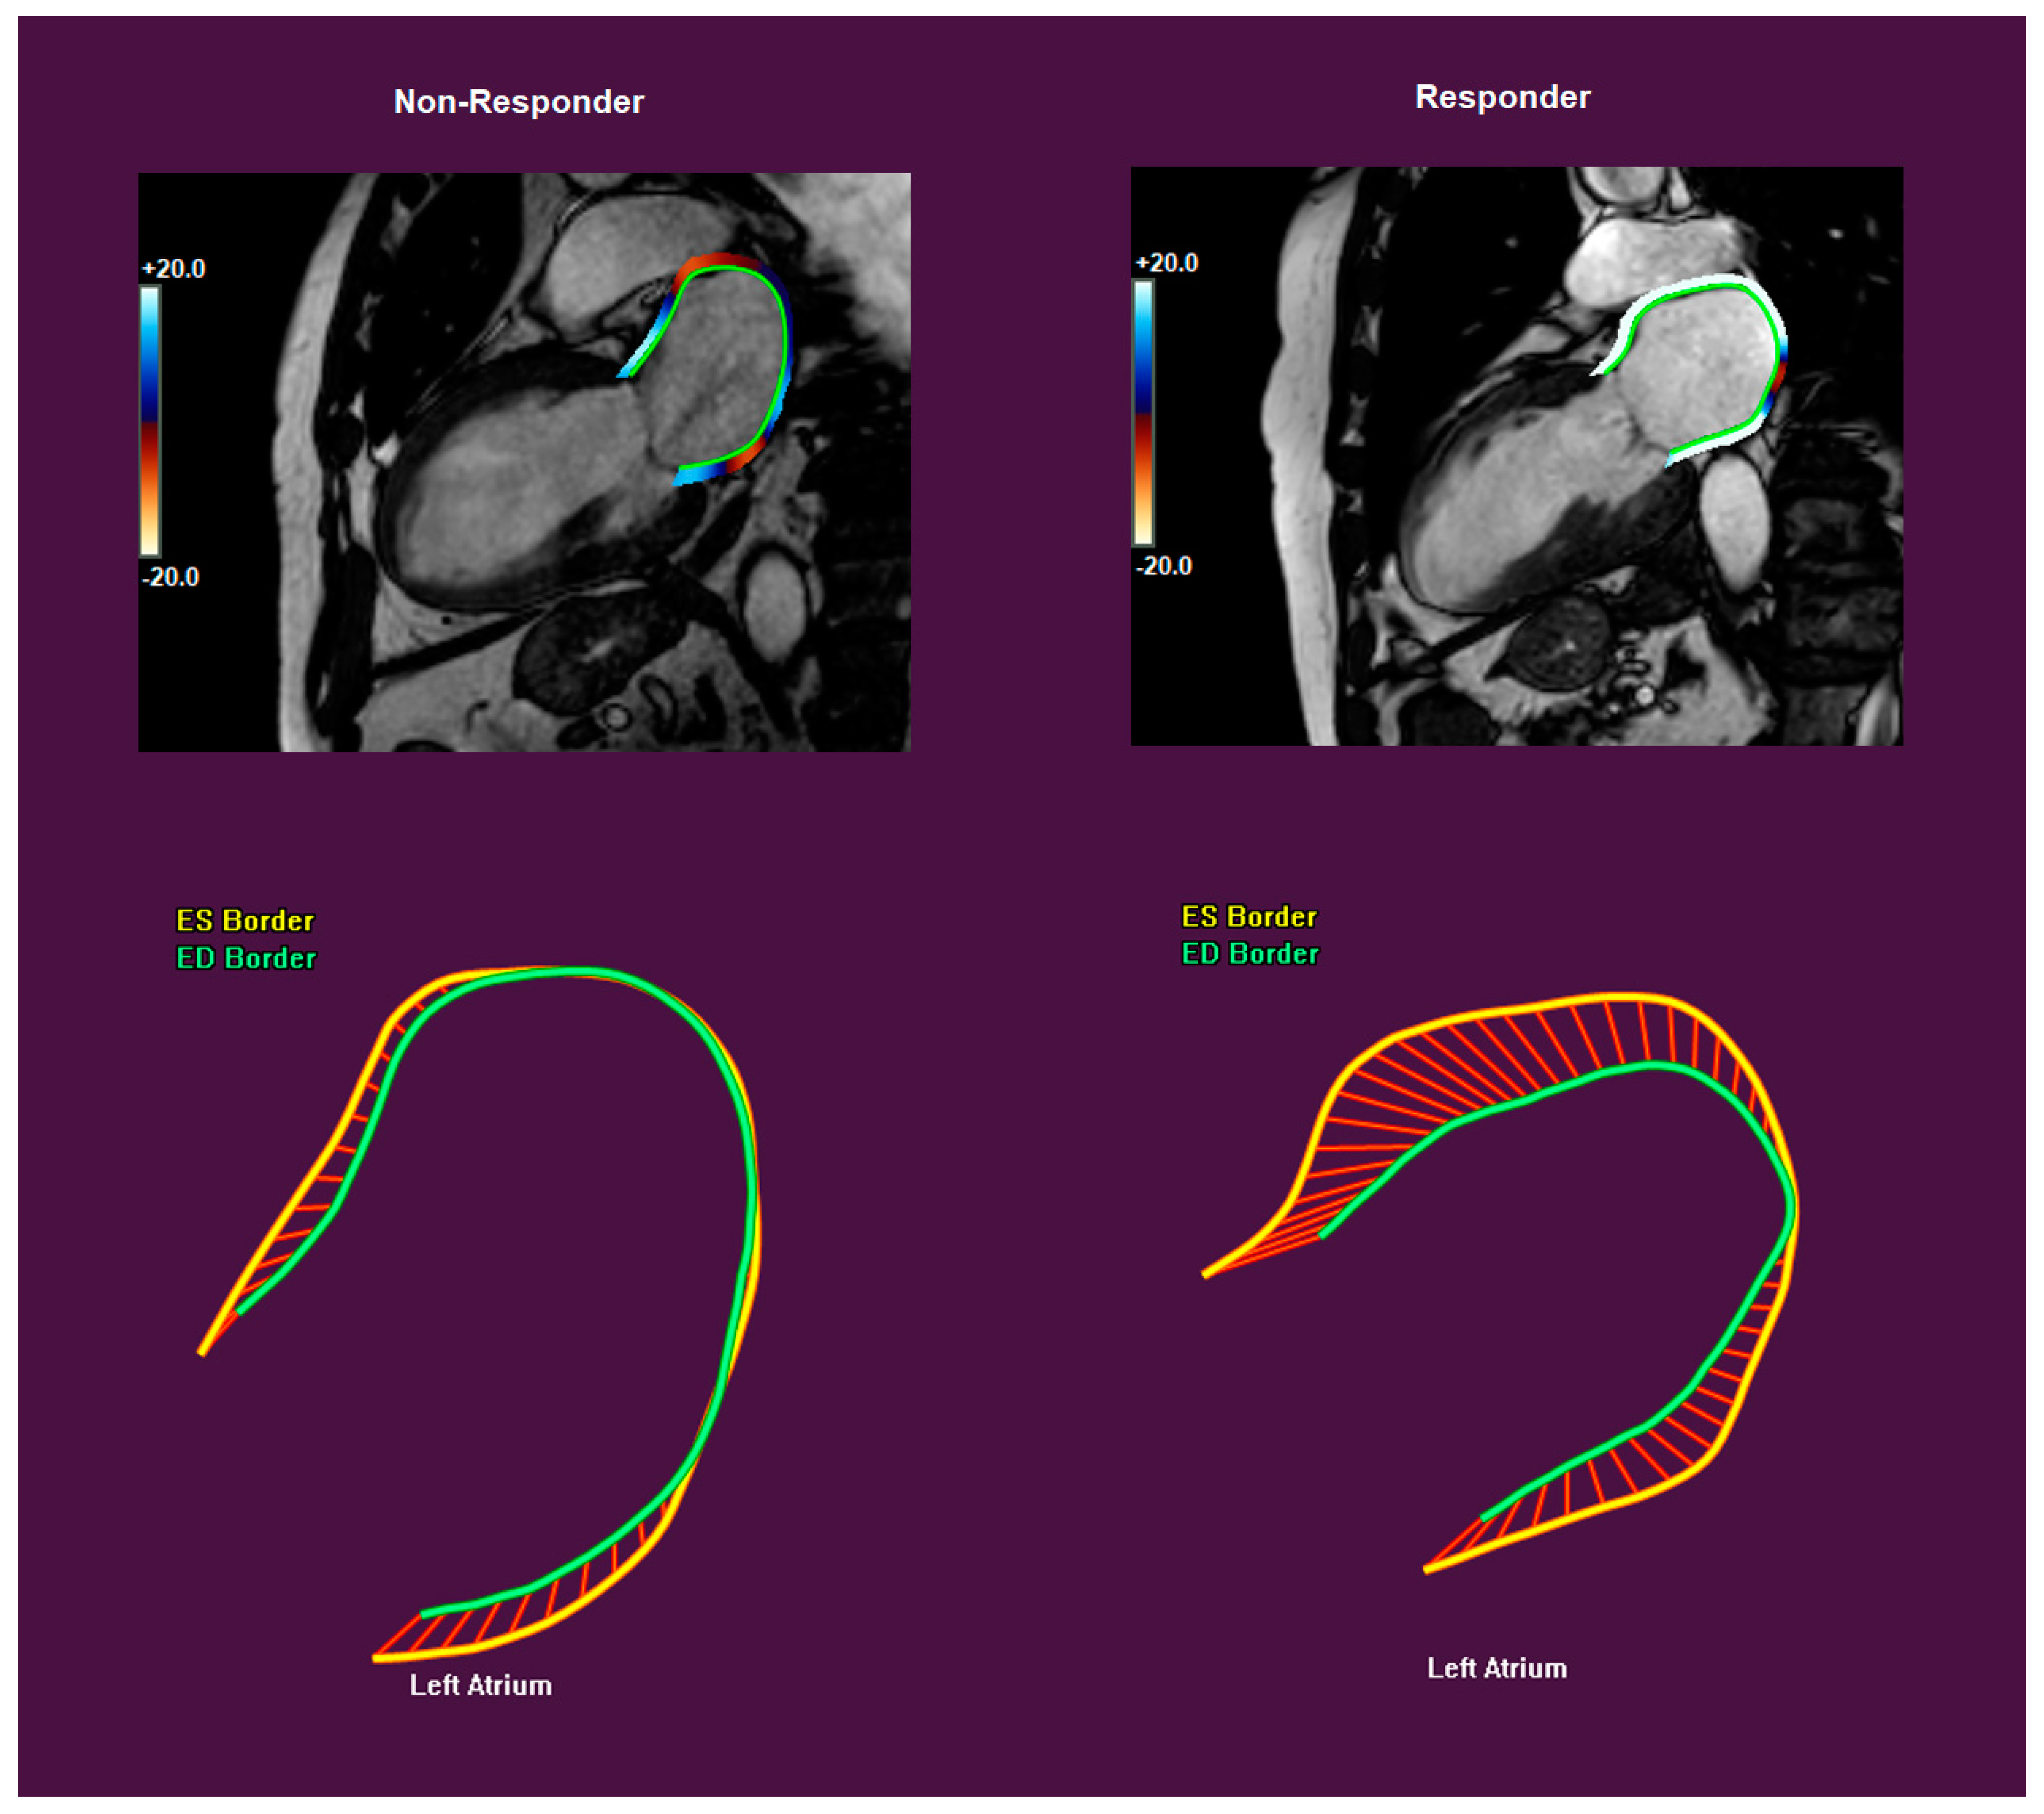

3.2. Strain Measurements and CRT Response

| RV GLS (%) | −22.8 ± 7.4 | −25.0 ± 6.5 | −18.9 ± 7.6 | 0.004 |

| RV free wall GLS (%) | −28.9 ± 8.9 | −31.1 ± 7.9 | −24.9 ± 9.5 | 0.017 |

| LA GLS (%) | 21.6 ± 11.3 | 25.1 ± 10.4 | 15.6 ± 10.4 | 0.002 |

| LA GCS (%) | 24.0 ± 15.0 | 27.9 ± 14.7 | 17.1 ± 13.1 | 0.012 |